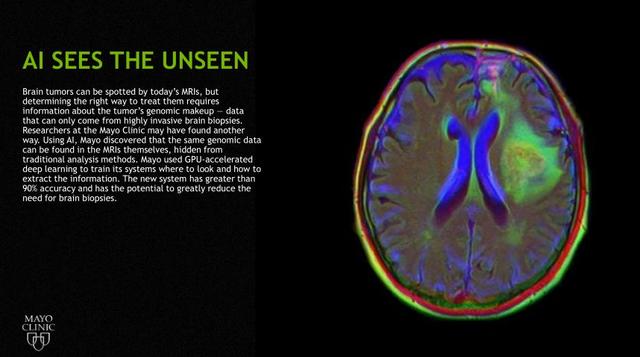

另外一个让人非常兴奋的领域是精准医学,上图右边展示的是脑部扫描图片。在面对某些脑癌的时候,医生有能力去判断需要什么药物,问题是医生不可能在大脑上打个洞,然后去切片,再去分析,现在通过脑部的MI扫描方式,用深度学习神经网络去判断和预测患者肿瘤突变的概率,目前准确度也超过了90%,使得医生可以用精准的药物去帮助病人做治疗,减轻他们的痛苦。

最后一个是用ML发现脑肿瘤,以前的做法可能需要直接打开头颅,然后打个孔,去看拿到的切片,看看里面是不是有肿瘤,及肿瘤状况。现在MAYO CLINIC使用GPU加速,可以用MRI的信息,以前用非深度学习方法发现不了的数据信息,去做一些比对,进而判断到底里面是不是有肿瘤,准确率也超过了90%,所以通过这样的方式,不仅可以把以前的结果做得更好,同时也可以做以前不能做的,而对于medical image(医学图像)我们需要怎样的一个平台呢?